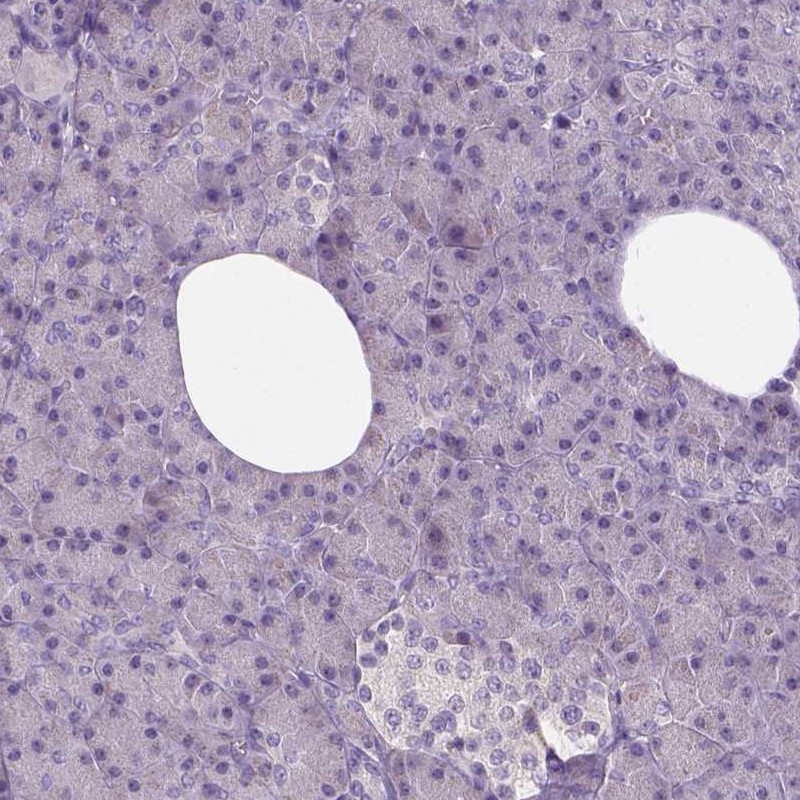

Immunohistochemistry analysis in human cerebral cortex and pancreas tissues using Anti-NLGN2 antibody. Corresponding NLGN2 RNA-seq data are presented for the same tissues.